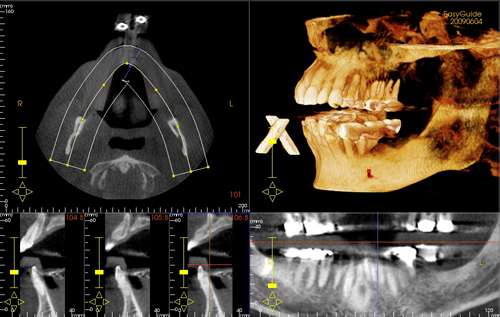

Photos of Dental Excellence of Rockledge, Robert Wilkoff, D.D.S.